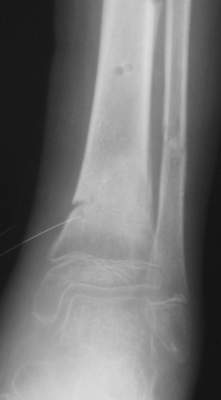

В январе 2005: варусная деформация н\3 голени, болевой с-м, комбинированная контрактура г\стопного сустава, нейропатия м\берцового нерва сохраняется слабость разгибания 1 пальца.

Операции: 1 Клиновидная резекция на вершине деформации м\берцовой кости.

2 Тугоподвижный ложный сустав н\3 б\берцовой кости. Рубцы выполняющие пространство между отломками, канал проксимального отломка иссечены.

Одномоментное устранение деформации, остеосинтез Г-образной пластиной.

Это сросшийся перелом малоберцовой кости. И ложный сустав

н\3 б\берцовой кости.